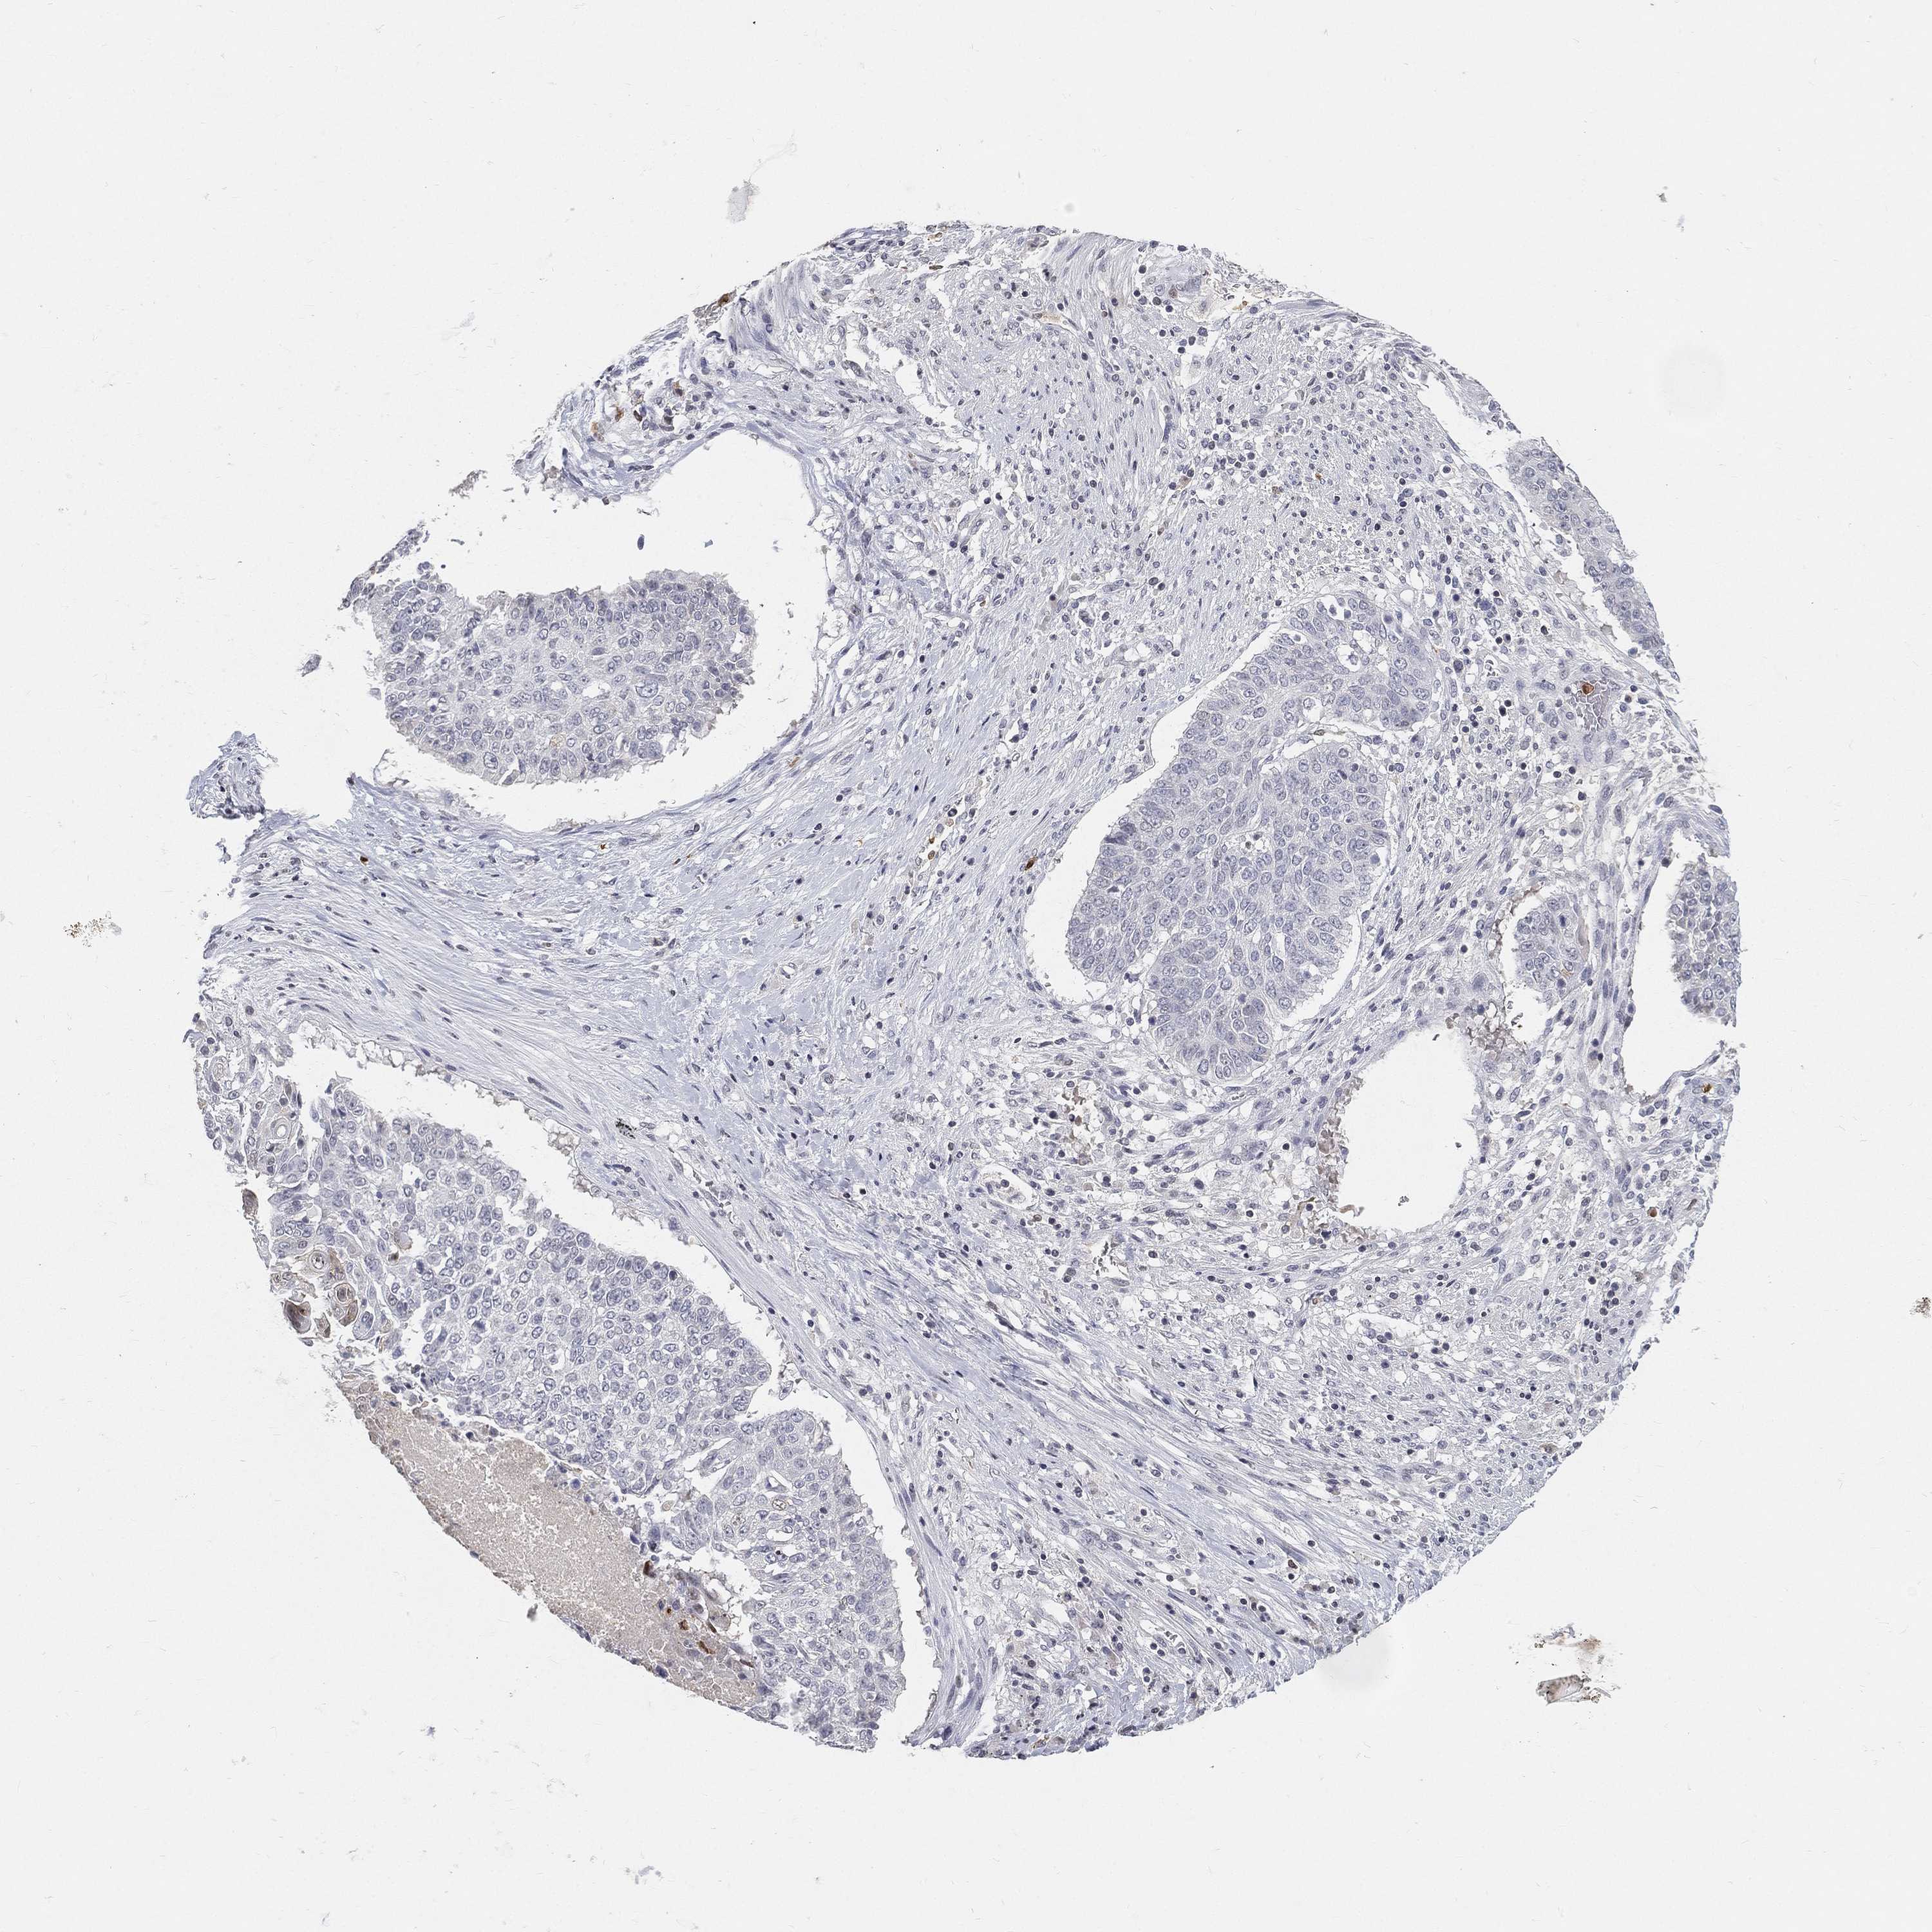

CANCER LUNG CANCER Show tissue menu

LUAD TCGA LUAD VALIDATION LUSC TCGA LUSC VALIDATION PROTEIN LUAD CPTAC PROTEIN LUSC CPTAC PROTEIN EXPRESSION